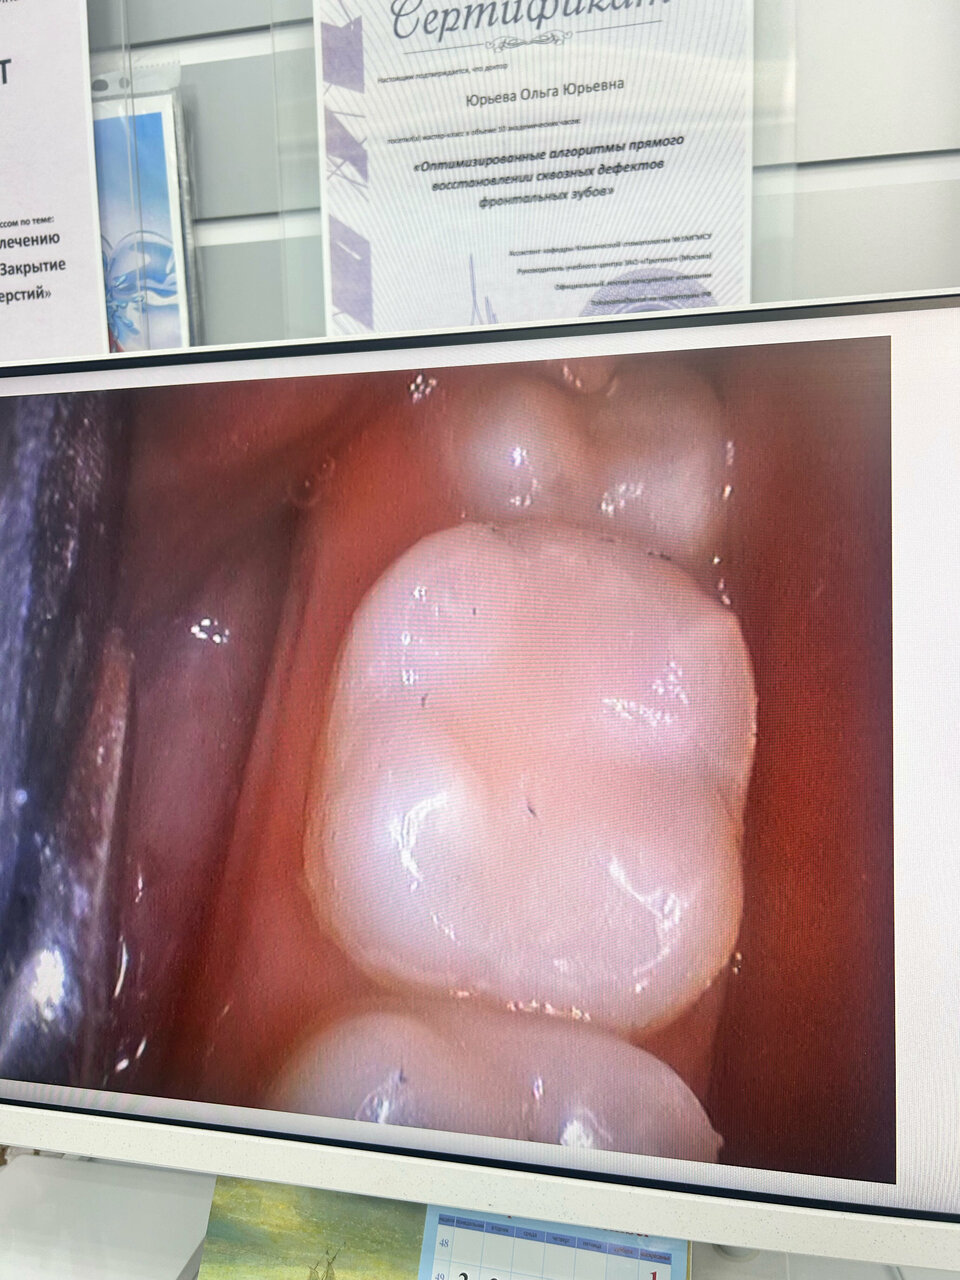

Сотрудничаю с этой клиникой с 2006 года и не разу не сожалела об этом!!! Лучшие специалисты Юрьевна Ольга Юрьевна, врач-терапевт красивая женщина и профессионал с большой буквы. Стоматолог-ортопед Артюхов Александр Владимирович, лучшее протезирование в городе!!!! Точность, аккуратность, профессионализм и замечательная улыбка. Здесь всегда рады помочь. Спасибо вам большое.

Много лет всей семьей лечимся у Юрьевой О.Ю. По нашей рекомендации даже друзья приезжают именно к ней с другого конца города. Ольга Юрьевна настоящий профессионал! Персонал клиники вежливый и отзывчивый. Всегда только приятные впечатления от посещения. + часто бывают интересные акции и скидки на услуги, есть бонусная программа.

Космостом — супер!!! Всегда рекомендую! Мы вместе уже почти 20 лет. Лечение,протезирование- на высшем профессиональном уровне. Каждый год приглашают на осмотр .С удовольствием приезжаю к Юрьевой Ольге Юрьевне! Это высококлассный специалист и просто добрая, милая женщина! Всем счастья и здоровья!

Замечательная стоматология, отдельное спасибо Ольге Юрьевне, отличный специалист

Более 10 лет лечусь в клинике Космостом у Юрьевой Ольги Юрьевны! Огромная благодарность доктору за доброту, заботу, тактичность и аккуратность!